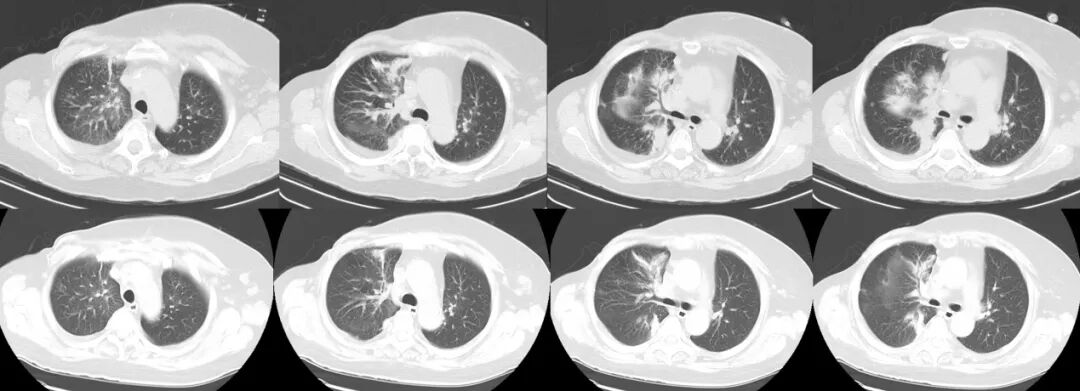

【學科風采】乳腺癌患者千里求醫(yī),成功治療多發(fā)腦轉移瘤、脊髓轉移、腦膜轉移、椎管內多發(fā)轉移結節(jié)、肺炎及肺門轉移患者